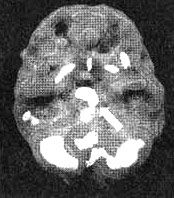

Трехмерное изображение снизу - активный мозг. Обратите внимание на повышенную активность в лимбической системе.

Провести его оказалось нелегко. Мы пытались провести сканирование три раза. Первые два раза она вырывала из вены иглу, утверждая, что мы хотим ее отравить. В третий раз нам удалось провести обследование, поскольку рядом стояла ее сестра, которая разговаривала с ней на всем протяжении процедуры. Результаты показали повышенную активность в глубокой лимбической системе, но не только. Я обнаружил очаги повышенной активности в левой части мозга и участки выраженного повышения активности по всей коре. Иными словами, в каких-то областях отмечалась повышенная активность, а в других - пониженная. Из своего опыта я знал, что циклические нарушения эмоционального состояния часто сочетаются с очагами повышенной активности в глубокой лимбической системе и с участками повышенной активности по поверхности всего мозга.

Мозг Сары - маниакально-депрессивный синдром